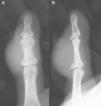

The case was a male patient, 65 years old, with no relevant medical history, who was consulted due to painless swelling on the dorsal side of the fifth finger of the left hand which had lasted for 4 years, with no history of trauma. Physical examination confirmed the tumor, elastic on palpation, with preserved finger mobility (Fig. 1) Simple X-rays showed a soft tissue tumor (Fig. 2); the ultrasound demonstrated the same lesion and the MRI showed a lesion measuring 16×10×12mm in diameter craneo-caudally, anteroposterior and transversely, unhomogeneous, with a hypointense signal and loculations on T1, predominantly hyperintense on T2 and showing moderate contrast enhancement (Fig. 3).

The lesion was diagnosed to be a giant cell tumor of the tendon sheath of the fifth finger and was removed in its entirety (Fig. 4). Two years later the lesion recurred (Fig. 5) and the patient underwent surgery. Currently, after two years, there have been no new recurrences, the mobility of the distal interphalangeal joint is limited, although the function of the patient's hand is normal.